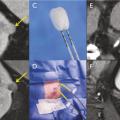

Pour chaque patient, un bilan d’hémostase est systématiquement réalisé avant la procédure. Pour les patients prenant des anticoagulants oraux, un relais par héparine de bas poids moléculaire est réalisé. Pour les antiagrégants plaquettaires, seul le clopidogrel doit être interrompu 5 jours avant. Le patient reçoit une prémédication par 1 g de paracétamol intraveineux 30 minutes avant la procédure. Il reste hospitalisé une nuit, mais une prise en charge ambulatoire est possible.La cryothérapie est réalisée sous anesthésie locale à l’aide d’un mélange de lidocaïne et de ropivacaïne. Contrairement à la radiofréquence ou aux micro-ondes où une seule électrode est insérée, la cryothérapie nécessite de mettre en place plusieurs aiguilles (cryoprobes) espacées au maximum de 15 mm afin de couvrir la totalité de la tumeur (fig. 1 ). Plus la tumeur est grosse, plus le nombre d’aiguilles à introduire est important. Il existe des abaques permettant de déterminer le nombre d’aiguilles optimal en fonction de la taille de la tumeur. Néanmoins, l’indication principale étant des tumeurs de stade T1a (< 4 cm de diamètre), le nombre moyen d’aiguilles est de 3, avec des extrêmes entre 2 et 5. Une injection de CO2 (carbodissection) ou de sérum physiologique (hydrodissection) est parfois nécessaire entre le rein et les organes adjacents afin de les éloigner de la zone d’ablation et les protéger.Les aiguilles sont mises en place sous tomodensitométrie et on vérifie leur bon positionnement. La dose délivrée lors d’une cryoablation rénale est inférieure aux niveaux de référence de dose recommandés pour une tomodensitométrie abdominale. Le traitement consiste en deux phases de cryoablation de 10 minutes entrecoupées d’une phase de réchauffement passif de 10 minutes également. L’effet cryogénique est obtenu par expansion d’un gaz (l’argon) dans une chambre de décompression de 2 à 4 cm de long située à l’extrémité de l’aiguille. Les températures minimales obtenues au contact de l’aiguille sont proches de -100 °C, en sachant qu’en moyenne la température de la tumeur se situe à -40 °C. La tomodensitométrie permet une excellente visualisation de la boule de glace, ce qui permet de monitorer l’ablation tout au long de la procédure. La boule de glace ainsi créée doit englober en totalité la tumeur et la dépasser de 5 mm afin d’avoir des marges de sécurité (fig. 2 ).6 En effet, le bord de la boule de glace est à l’isotherme 0 °C, qui n’est pas létal pour les tissus.Après traitement, le suivi des patients s’effectue par tomodensitométrie ou par imagerie par résonance magnétique (IRM), typiquement à 1 mois, 3 mois, 6 mois et 1 an, puis tous les ans. La zone d’ablation se rétracte progressivement et se fibrose, sans tumeur résiduelle visible (fig. 3 ). Pour les tumeurs de moins de 2 cm, le zone d’ablation disparaît parfois en totalité, laissant juste une encoche à la surface du rein (fig. 4 ). Les effets secondaires sont rares, la cryoablation étant mieux tolérée que les techniques d’ablation fondées sur le chauffage des lésions, en particulier pour les lésions proches de la voie excrétrice.7